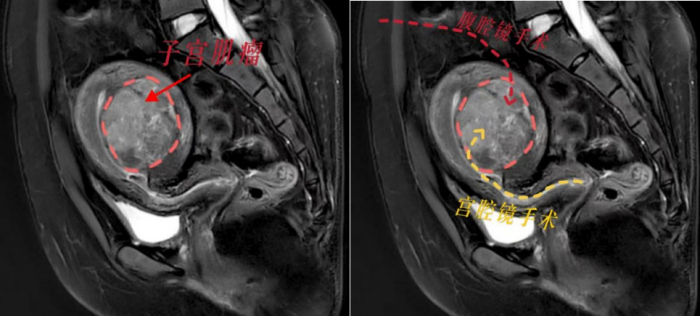

根据小丽的病情,香港马会app 妇产科三区副主任魏馨分析,宫腔镜手术无需腹部切口,通过自然腔道进行,切除肌瘤无需切开子宫肌层,能最大程度保护患者生育力。但是根据子宫肌瘤诊治专家共识,像小丽这样的病例并不适合宫腔镜手术,因为手术风险极高,难以一次性切除干净,还可能引发水中毒、子宫内膜损伤等严重并发症。而如果选择腹腔镜下子宫肌瘤剥除术,就必须把子宫肌层完全切开,术后至少需要等待1年才能怀孕,且怀孕后子宫破裂的风险极大。这对于渴望成为母亲的小丽来说,无疑是沉重的打击。

面对患者强烈的生育需求,魏馨主任带领团队迎难而上,决心挑战“不可能”!经过反复研究病情和推敲手术方案,魏馨主任凭借丰富的临床经验和精湛的宫腔镜手术技巧,成功为小丽实施了高难度宫腔镜下子宫肌瘤切除手术。手术不仅一次性将肌瘤彻底切除,而且没有损伤子宫肌层和内膜,术中出血少,术后恢复快,未出现任何并发症。术后第2天,小丽便顺利出院,术后3个月即可备孕,重燃了她成为母亲的希望。